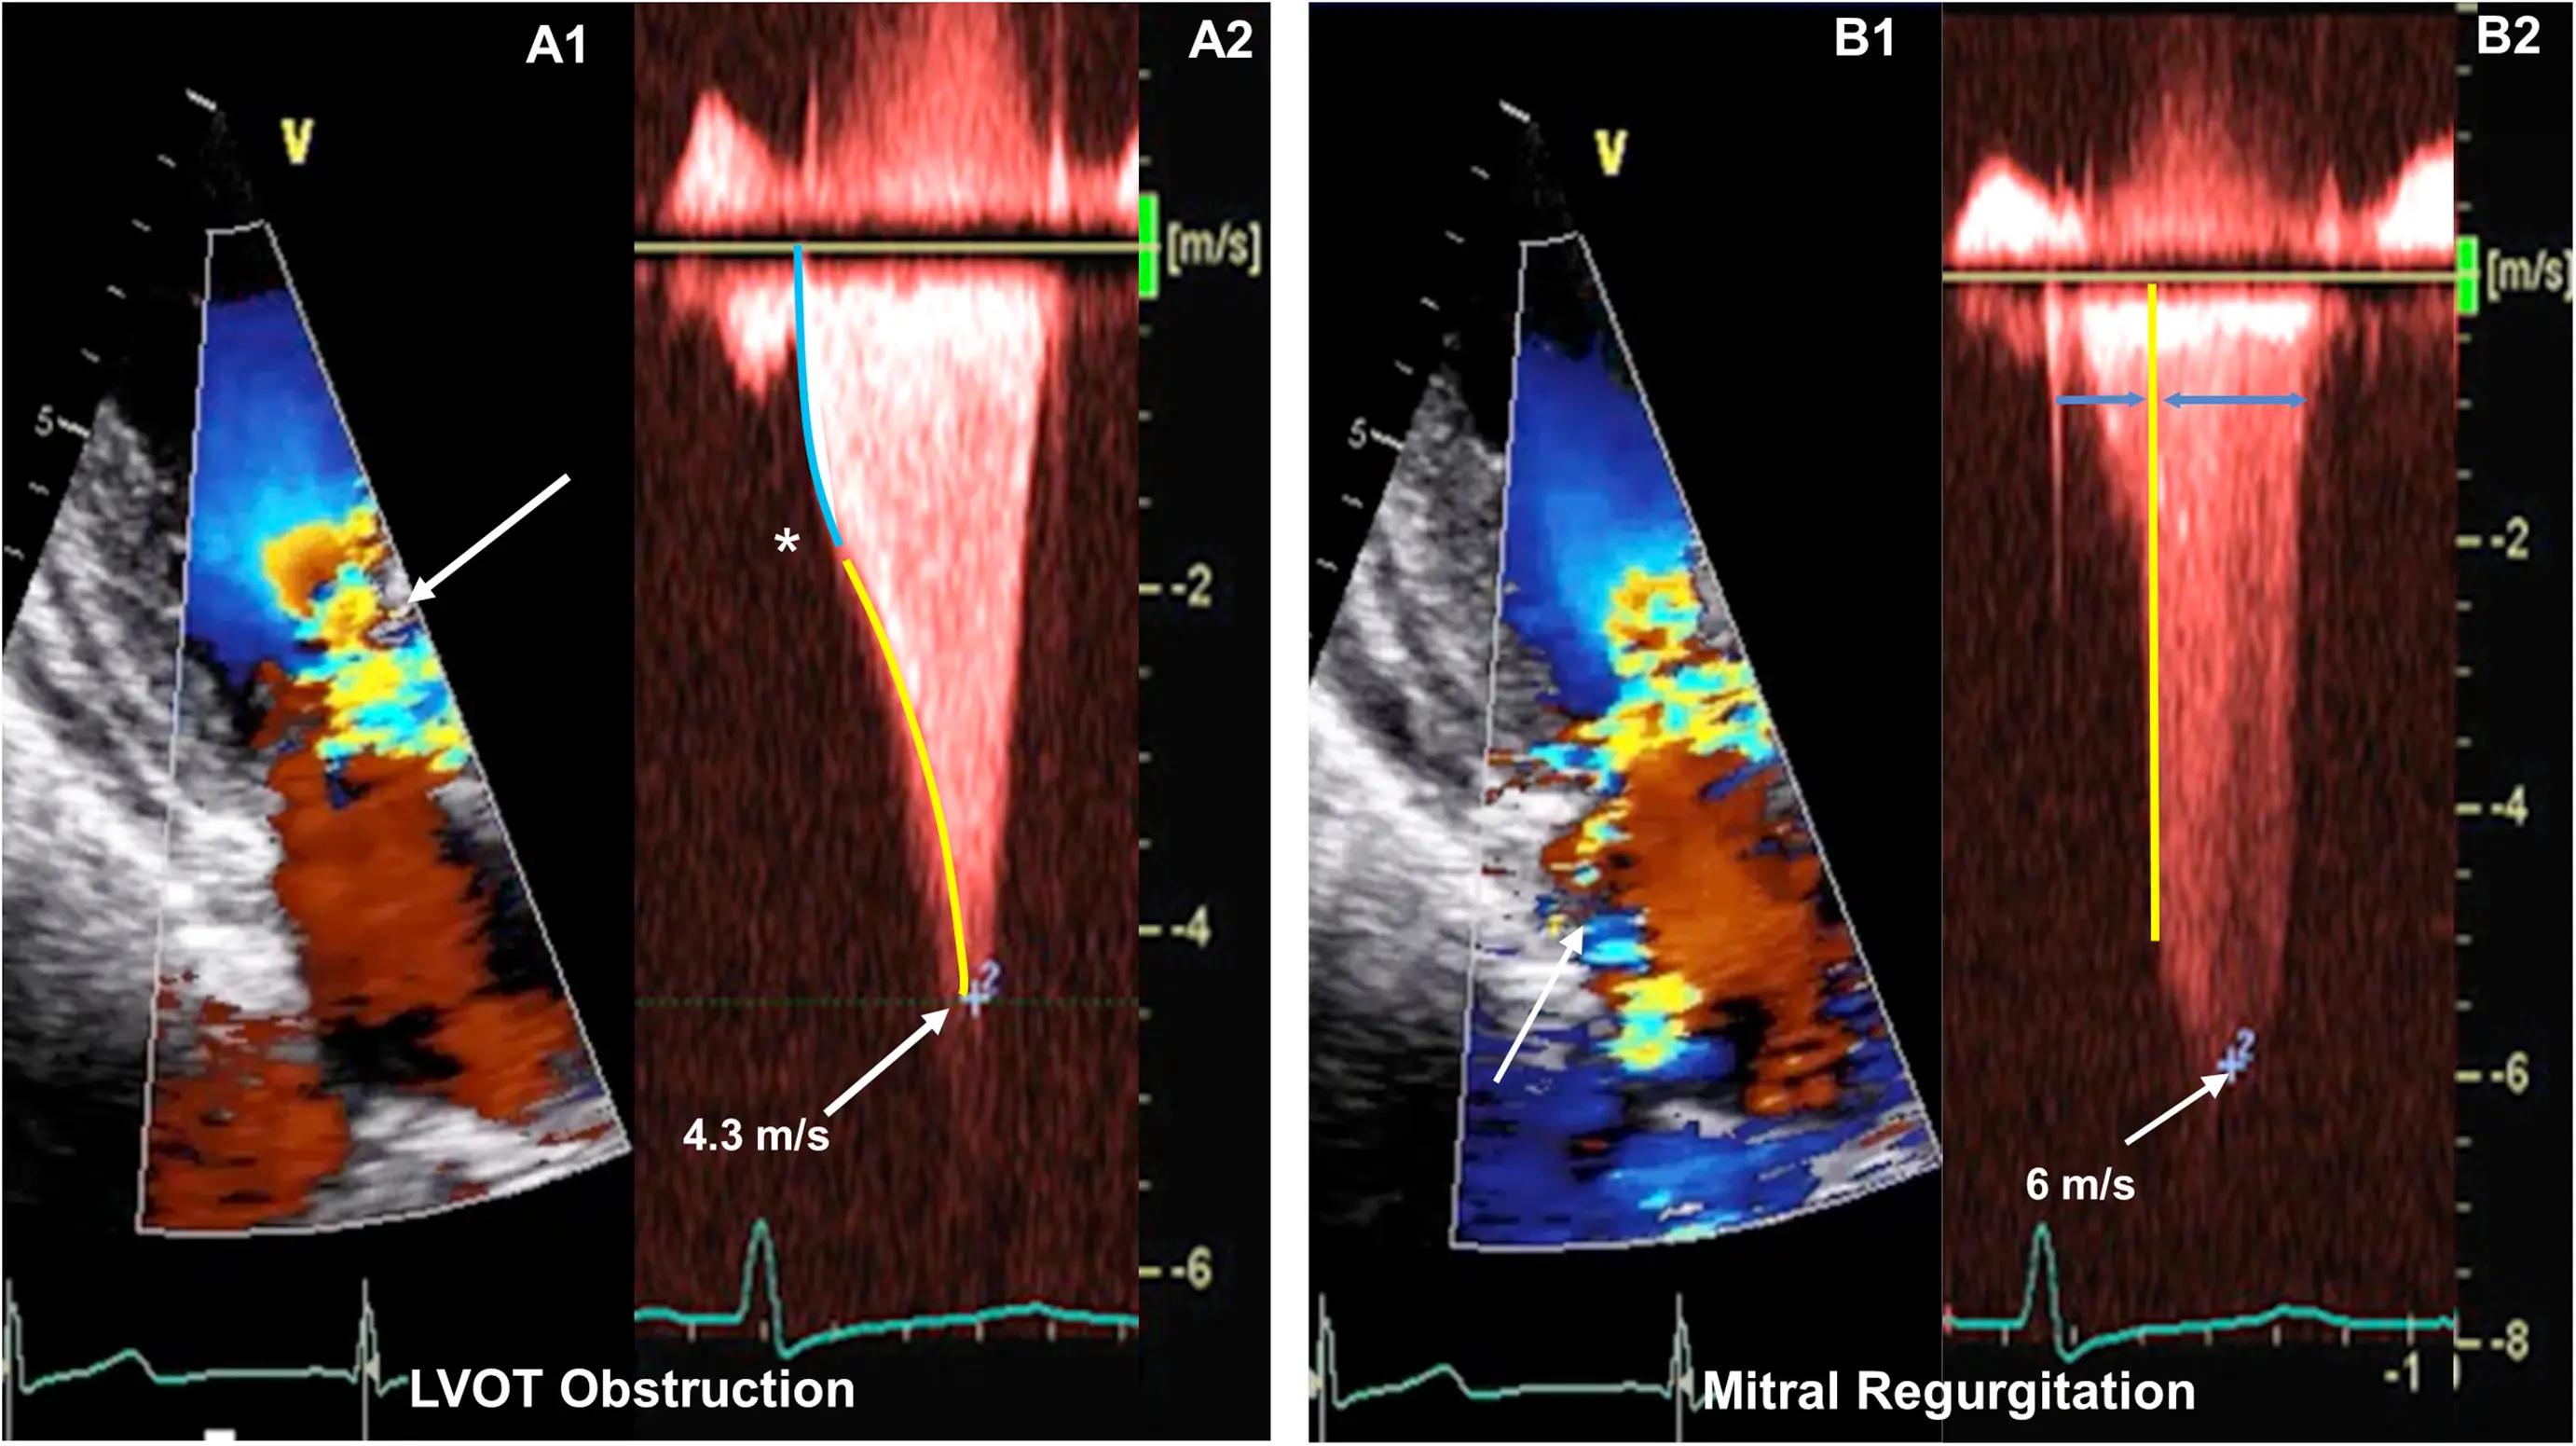

Classically described as having a “dagger”-shaped appearance, but honestly resembles more of a nonworking upper edge of a Bowie knife. 2 Dr. Saghir also used the term “dragon’s tooth,” which I like.

Gradients > 60 mmHg may take on a “lobster claw” pattern 2

- Calculate LVOT gradient using the peak velocity using the simplified Bernoulli equation

- Calculate LVOT gradient using the MR velocity

For example, MR peak velocity 8 m/s, estimated LAP 15 mmHg, SBP 98 mmHg

We can then use this value to quantify the LVOT gradient